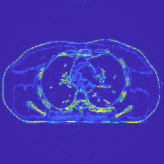

Fig. 7 studies the influence of regularization parameters and on PWLS-ST-. Given a fixed hard-shrinkage parameter , a larger value better removes noise (or unwanted artifacts), but too large can oversmooth reconstructed images; compare Fig. 7(a) and Fig. 7(b). Given a fixed regularization parameter , a larger value leads to lower sparsity in sparse codes and achieves better noise reduction, but too large can remove some edges (e.g., in bone regions); compare Fig. 7(c) and Fig. 7(d). In particular, Fig. S.8 in the supplement shows that once the value is properly chosen, PWLS-ST- is robust to a wide range of values.